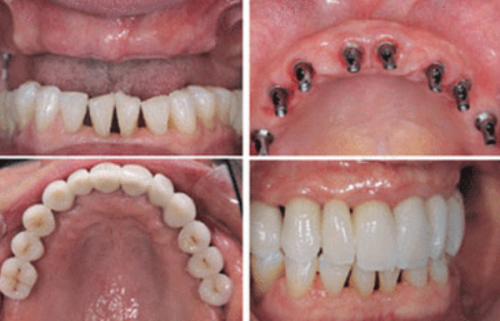

种牙,简单来说,就是把人工牙根植入牙槽骨内,等人工牙根和牙槽骨长在一起后,再安装上牙冠,这样就完成了牙齿的修复。这个人工牙根就相当于真牙的牙根,能给牙冠提供稳定的支撑,让牙齿就像真牙一样结实耐用。

烤瓷牙是通过把缺失牙两边的健康牙齿磨小,然后做一个连冠套在磨小的牙齿上,以此来修复缺失的牙齿。它主要是依靠两边的基牙来固定和支撑,就像搭桥一样,所以也叫烤瓷桥。

1. 连缺多颗牙:如果是连缺 6 颗牙这种情况,种植牙比镶烤瓷牙要好些。做种植牙只需植入 3 - 4 颗种植体加上连桥冠,就可以完成修复,而且咀嚼力度、咬合力量都比较好。而镶烤瓷牙需要选择至少两个健康的基牙搭桥,当缺失牙齿数量较多时,可能会面临基牙不够或者基牙不健康的问题,修复成效不理想。